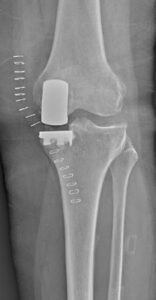

Intervenția chirurgicală a fost efectuată de echipa Secției Ortopedie Protetică a Articulațiilor Mari, condusă de șeful secției, Alexandru Bețișor. Potrivit medicului, pacienta a beneficiat de protezare parțială unicompartimentală a genunchiului, o procedură minim invazivă prin care este înlocuită doar partea articulației afectată de artroză. Tehnica permite păstrarea cartilajului sănătos și a ligamentelor încrucișate, ceea ce contribuie la menținerea unei mobilități mai naturale a genunchiului și la o recuperare mai rapidă.

Pacienta spune că a început să meargă chiar din a doua zi după intervenție.